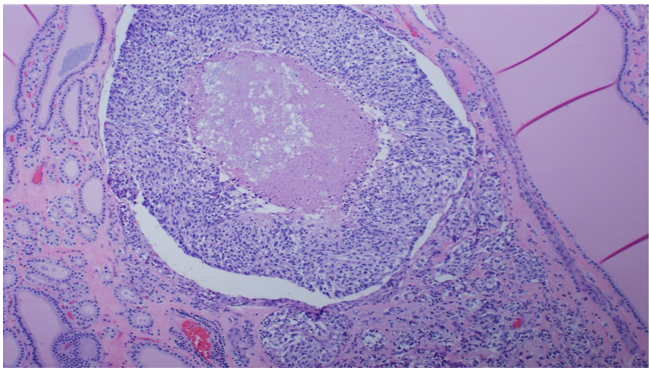

An isthmusectomy was performed with complete excision of the isthmus nodule and a small surrounding margin. The final pathology results from this excision revealed an “isthmus nodule” and consisted largely of benign hyperplastic follicles with a greatest dimension of 2.7 cm. In three microscopic foci (largest 3 mm), a proliferation of round to spindled neoplastic cells with well-dispersed nuclear chromatin and cleared cytoplasm were seen forming trabeculae within a dense hyalinized background. In the largest tumor focus, there was a nodule of briskly proliferative neoplastic cells with central necrosis (Figure 1).

Figure 1: Proliferation of round to spindled neoplastic cells with well-dispersed nuclear chromatin and cleared cytoplasm.